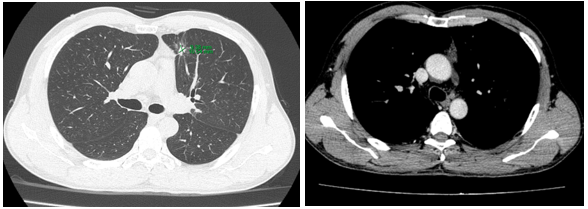

-         Chụp cắt lớp vi tính lồng ngực: phim trước điều trị

Hình 1. Trên phim chụp CT lồng ngực ở cửa sổ nhu mô: thùy trên phổi trái có khối đặc tròn bờ tua gai, kích thước: 29 x20mm, kính mờ và dày kẽ xung quanh, lân cận có nốt bán đặc kích thước 29 x 17mm, ngấm thuốc không đồng nhất sau tiêm, nghi ngờ có phần xâm lấn trung thất trước. Nhu mô thùy còn lại và nhu mô phổi phải lan tỏa các nốt đặc tròn to nhỏ không đều, đường kính: 2-8mm.

Hình 2. Cửa sổ trung thất: Vài hạch trung thất cạnh khí, hạch lớn nhất kích thước 14x7mm